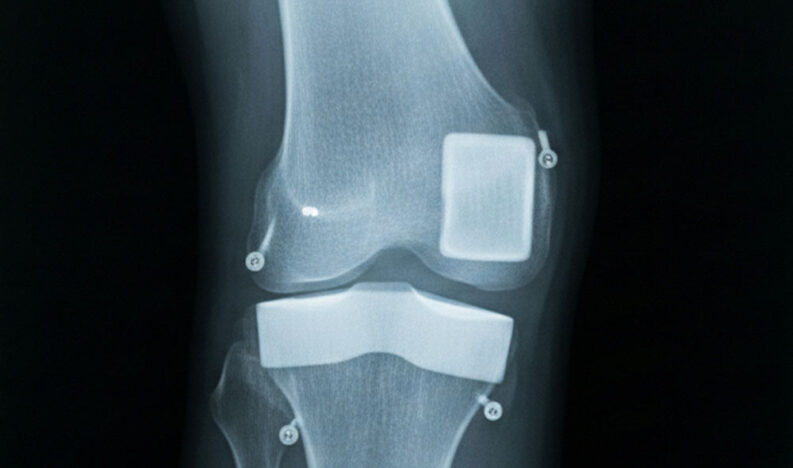

Knee Replacement Surgery